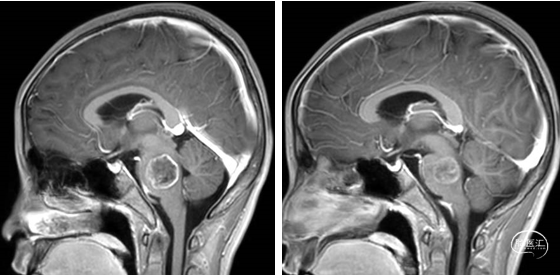

术前MRI

术后MRI